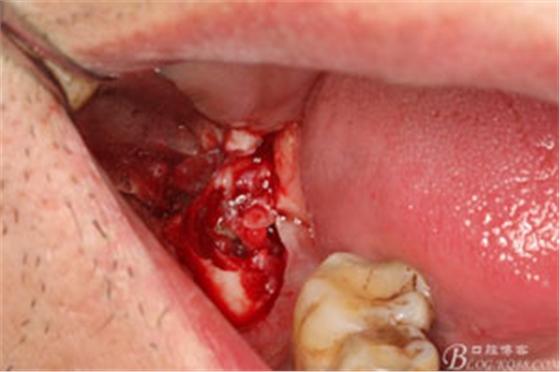

圖7.高速牙鉆去骨。逐漸可見48的牙冠

圖8.刮除牙冠表面的肉芽組織后,可見48 的牙冠